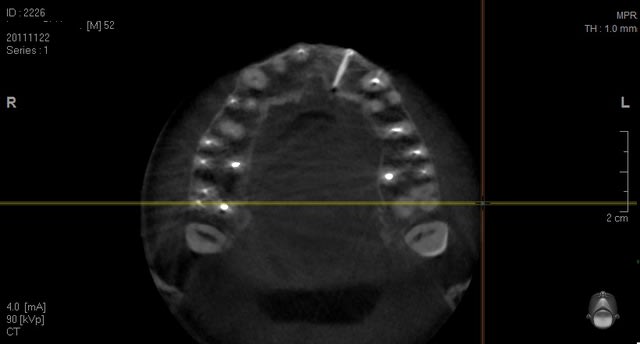

voilà des images de tout les jours....

Chevrier ecfaxb - Eugenol

Chevrier2 arpqfz - Eugenol

Guyot pr 2 pqmexp - Eugenol

Guyot pr 3 rztfoz - Eugenol

Scan greffe jzynvr - Eugenol

Scan greffe2 meswpp - Eugenol